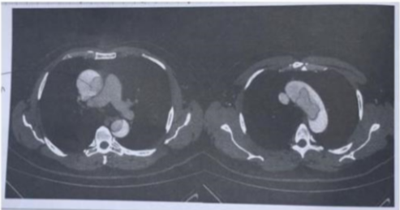

Homem, 60 anos de idade, apresenta dor torácica retroesternal de forte intensidade há cerca de 1 hora. Refere antecedente pessoal de hipertensão arterial. Ao exame clínico a ausculta pulmonar e cardíaca estão normais. Pressão arterial de 168 x 96 mmHg, frequência cardíaca de 80 bpm, frequência respiratória de 20 irpm, temperatura de 36,7ºC e saturação de 98%. Foram realizados eletrocardiograma e tomografia de tórax, exibidos a seguir. Qual deve ser a conduta neste momento?